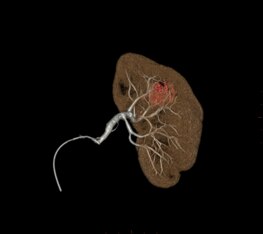

Planifier